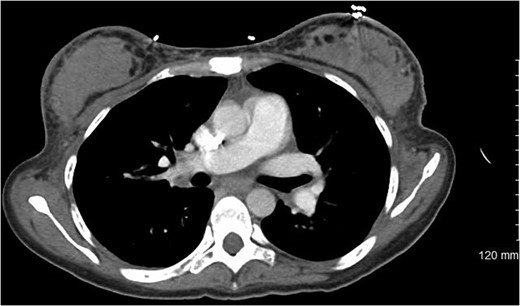

Evaluation of anemia and thrombocytopenia began with exploration of common causes. Mean corpuscular volume was 106 fl, red blood cell distribution width 30%. Manual blood count showed moderate polychromasia with both microcytic and macrocytic red blood cells. Schistocytes were visualized on blood smear. Haptoglobin was low (<15 mg/dl), while reticulocyte count was elevated (12.9%). Total iron and ferritin were both elevated (262 µg/dl and 1032 ng/dl, respectively). Vitamin B12 was elevated while folate was within normal limits. Initial imaging included computed tomography of her chest, abdomen and pelvis, which revealed diffuse skeletal metastases, masses in both breasts, hepatosplenomegaly and mesenteric stranding with trace ascites (Figs 1 and 2).

Computed tomography showing bilateral breast densities, showing nearly symmetric involvement of the entirety of each breast with no apparent chest wall or skin involvement.